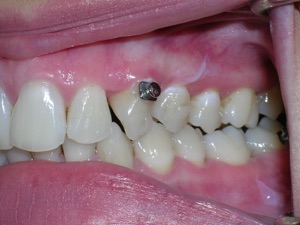

And more.

Needless to say, we were both quite happy with the outcome. Using elastics we were able to push back the back teeth and create space for the two teeth stuck behind.